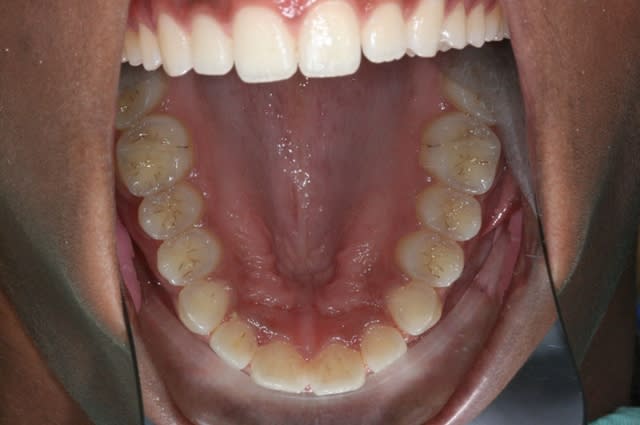

ou comme celui-là

(évidemment, c'est le m après TTT.)

C'est un bel alignement des dents, une esthétique correcte.

Mais l'occluso ne se fait pas sur des photos. Il y a de plus des indices que ça va pas être simple.

meilleur alignement, mieux esthetiquement et sans doute fonctionnellement qu'au départ mais insuffisant, il manque la finition.....

Donc ce cas est pour moi non terminé car en supraclusion anterieure, il y a une deviation des milieux et sans doute tout une histoire de tensions musculaires inadequates tant au niveau des masticateurs que de la langue. Les contacts dento dentaires on les a pas et je serais curieux de voir comment ça engrenne (des bouts de cuspides bien dans les fosses ou des bouts à bouts par ex...).

Bref joli cas, joli mais sans aucune certitude quand à son fonctionnement immediat et futur.